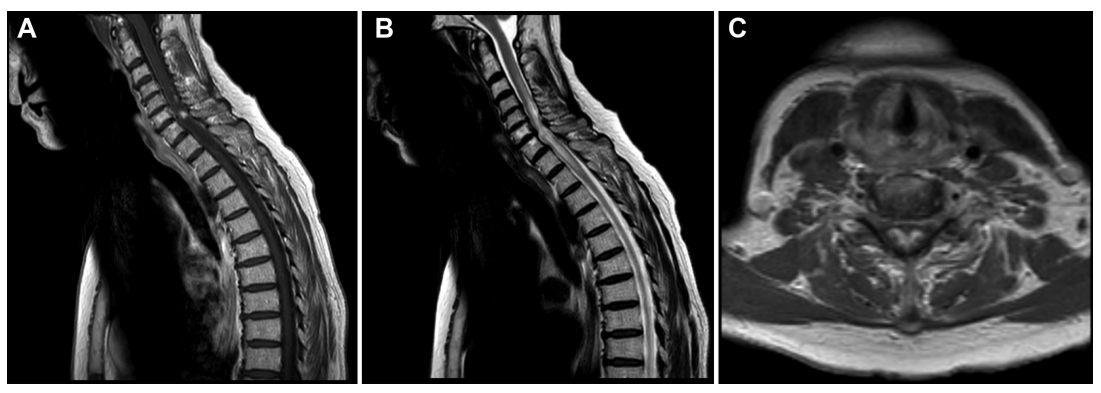

这位42岁的男性患者在神经外科手术前曾出现足底麻木,并伴有左大腿感觉异常和轻微的膀胱疾病,图为其影像学表现。

神经学检查进一步显示伴肌张力和反射增强的准痉挛。MRI显示在Th4和Th5高度的中央髓内弱环形强化病变。经跨学科肿瘤委员会讨论后,建议进行神经外科干预。